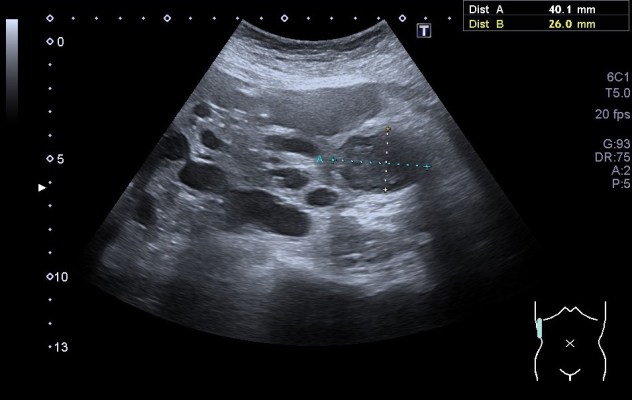

Categoría 3: Masas indeterminadas, sospecha moderada de malignidad en torno al 50%:

1. Engrosamientos de algún tipo sobre todo en septos intraquísticos

2. Realce medible con contraste en TC y RMN.

3. Son malignos entre 40 y 60 de cada 100.

4. El resto de los benignos son hemorrágicos o infectados.

5. Necesitan cirugía.

En el contexto de una poliquistosis renal, algunos elementos pueden cambiar de aspecto, la vigilancia de estos es obligada y la dificultad cuando existen tantos se hace evidente.